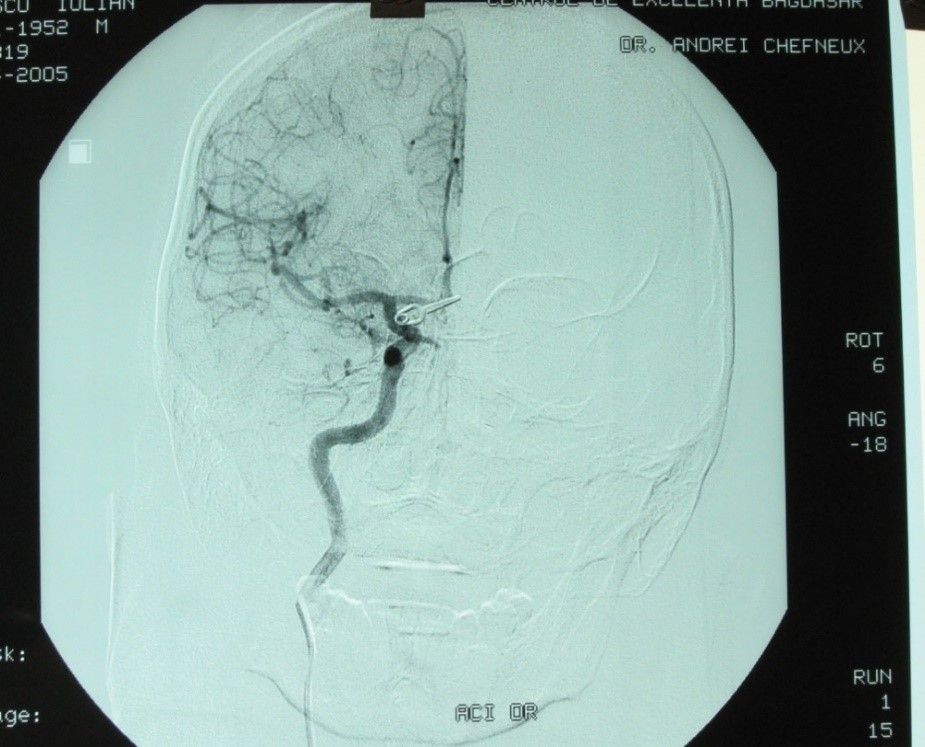

- solide – PVA (alcool polivinil), fibre, coils (mici spirale metalice), balonaș (fig. 2);

Fig. 2. Anevrism embolizat de arteră comunicantă posterioară; din arhiva personală a dr. C. Mihalea).